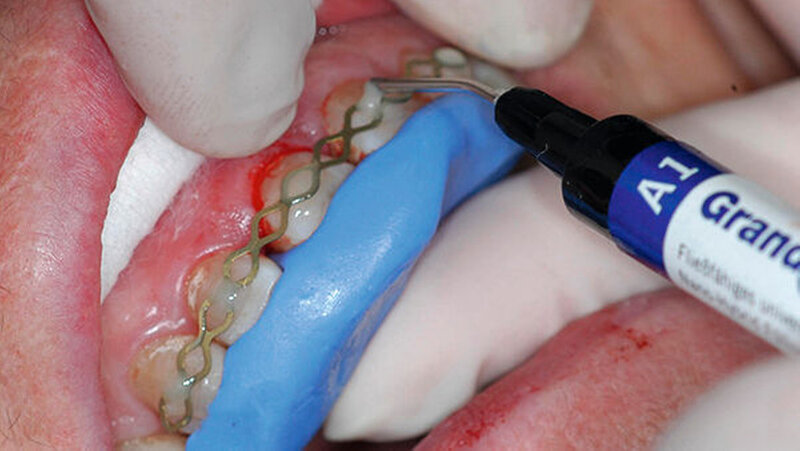

Anschließend wurden diese Defekte mithilfe eines Dentinhaftvermittlers (Optibond All-In-One; Kerr, Orange) und einer Kompositrestauration (Grandio/Grandio Flow; VOCO, Cuxhaven) versorgt, um den Zahn sowohl koronal als auch intrakanalär zu stabilisieren. Nach Entfernung des Kofferdams und Herstellung eines Silikonschlüssels wurde eine Titan-Trauma-Schiene (TTS; Medartis, Basel) angepasst und der Bereich mithilfe einer Infiltrationsanästhesie anästhesiert.

Während die palatinale Fläche unbeschädigt war, zeigte die bukkale Fläche eine vertikale Frakturlinie (Abbildung 3), die mit einem feinen diamantierten Schleifkörper erweitert wurde (Abbildung 4). Zusätzlich erfolgte die Entfernung des retrograden Wurzelkanalfüllmaterials. Beide Defekte wurden mit Biodentine (Septodont, Niederkassel) aufgefüllt (Abbildung 5).